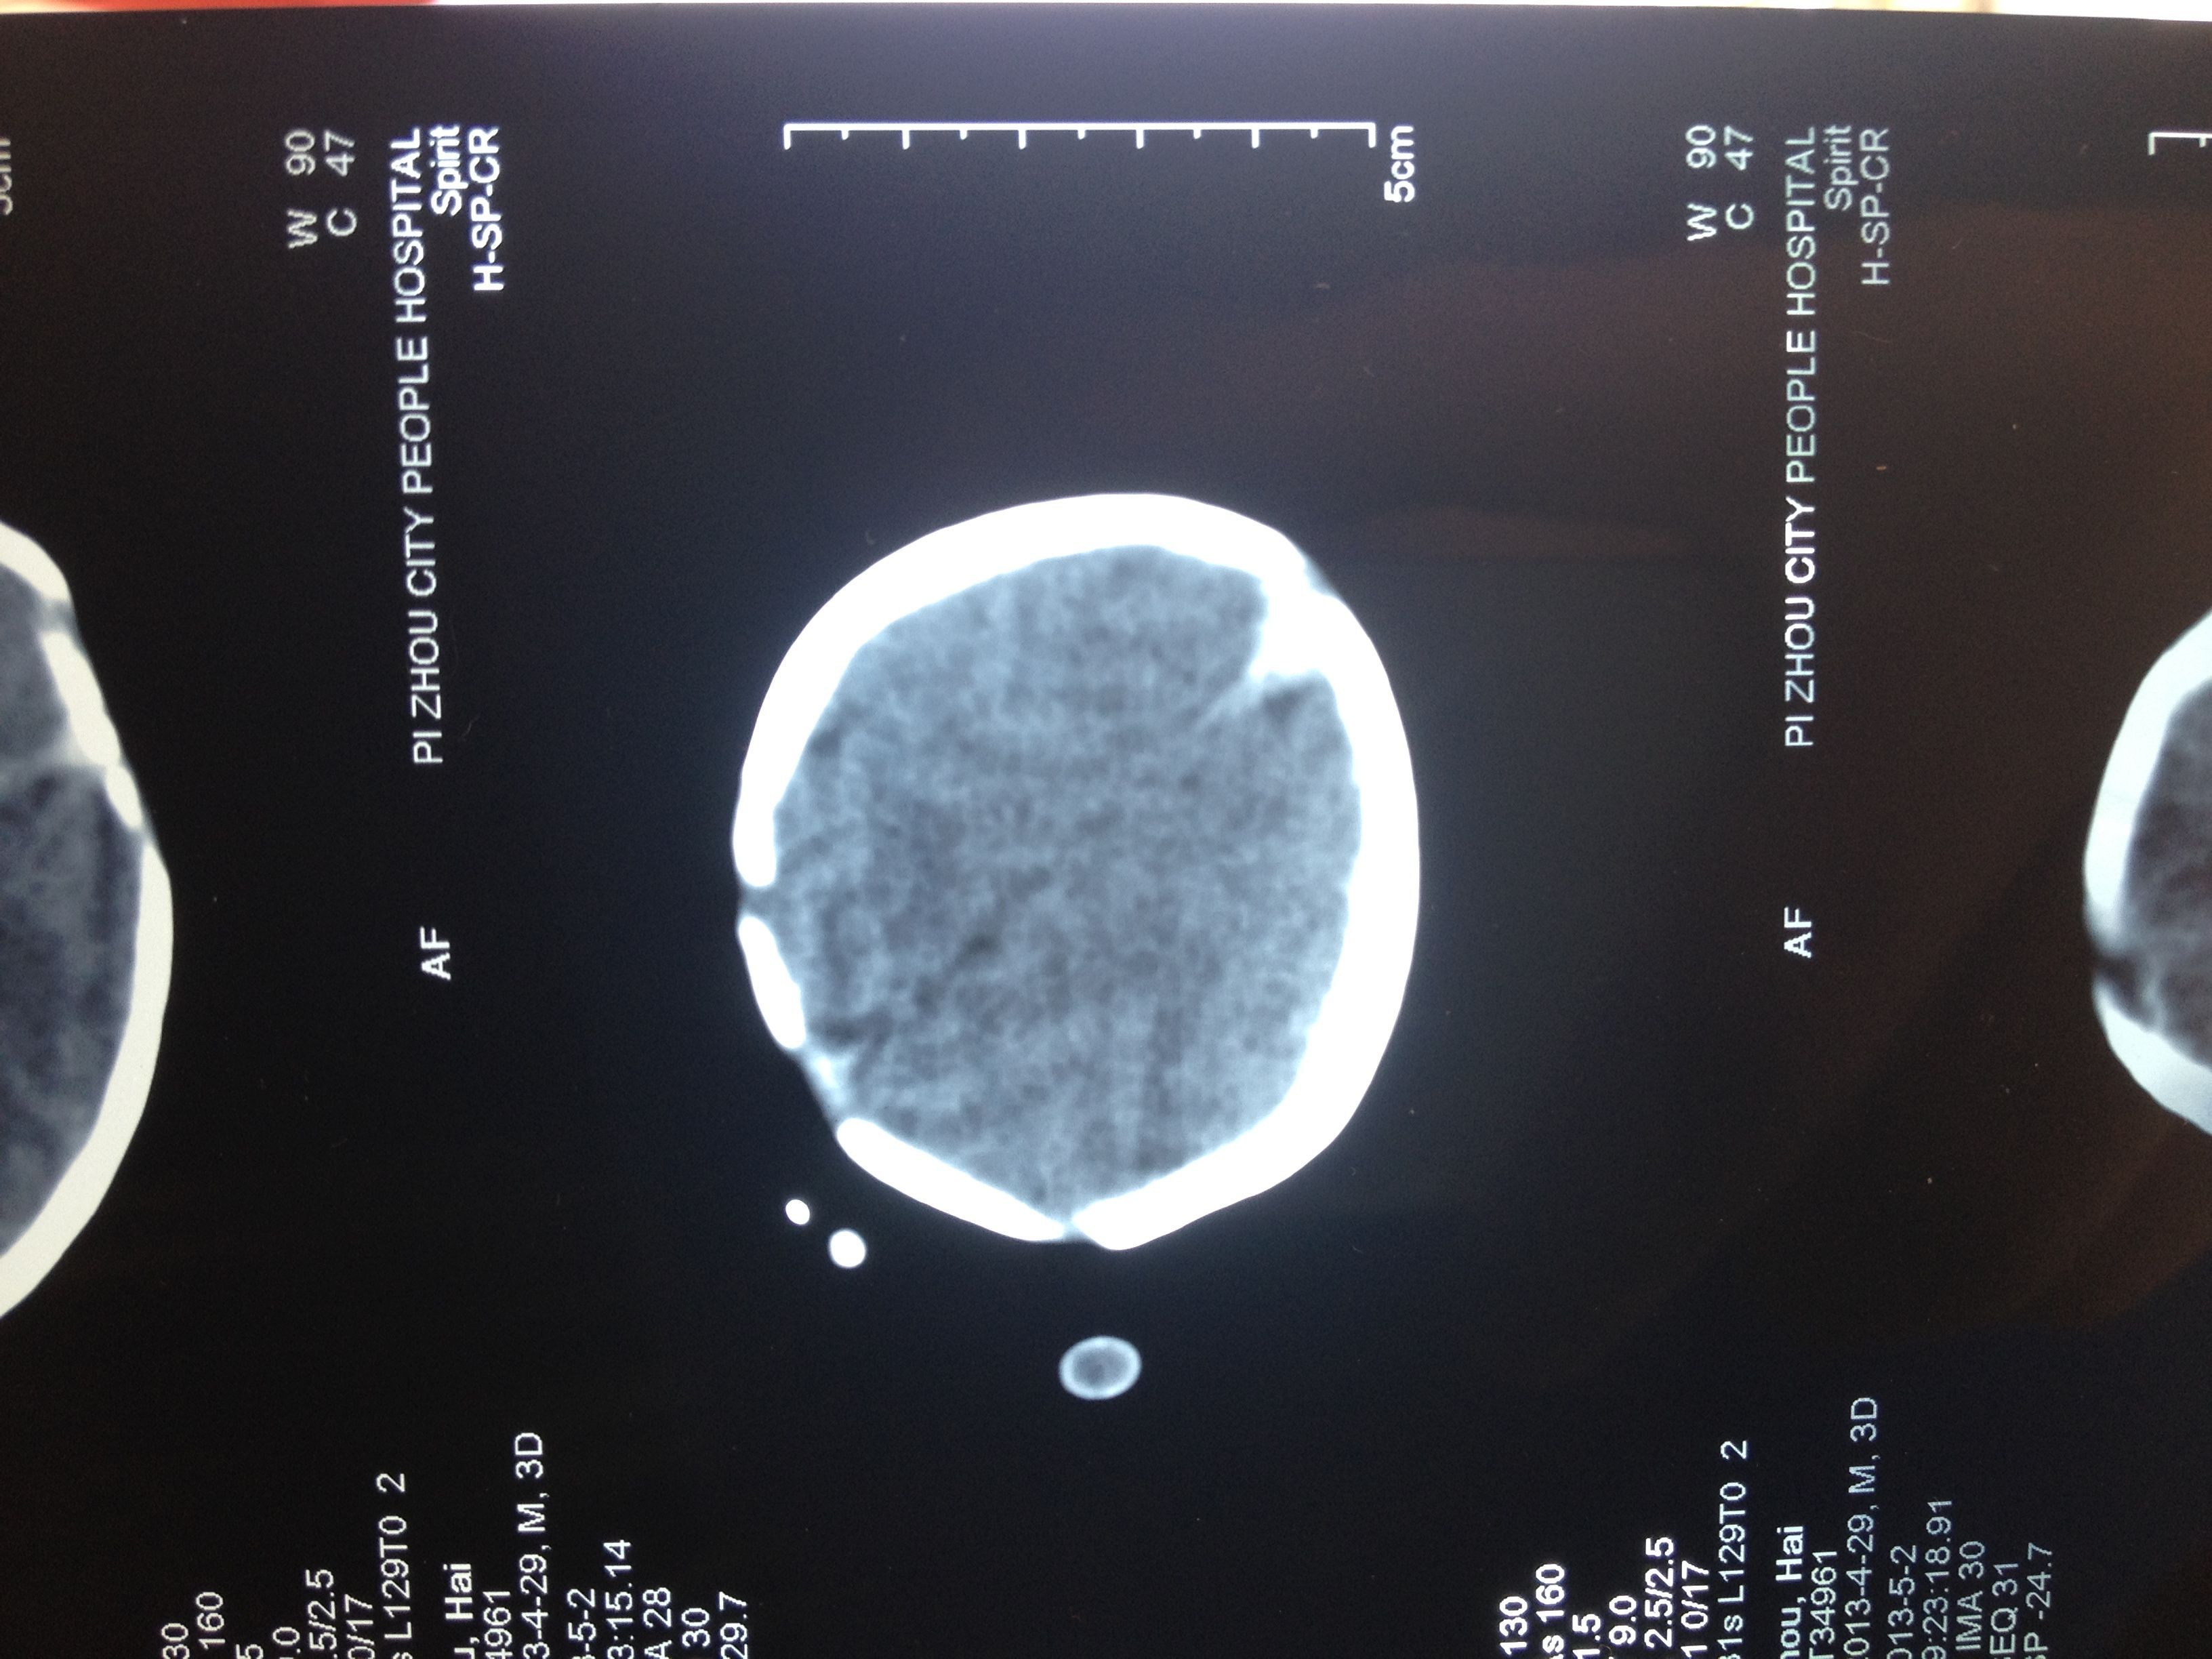

新生儿颅脑平扫CT图片 懂得来看一下 点击展开 匿名用户 2013-05-05 09:58 为您推荐: 其他回答 但从这一张上看不出什么明显的问题 不过不能排除 新生儿缺氧引起的脑损害 也就是缺血缺氧性脑病 大医精诚01 2013-05-05 10:00 相关问题 新生儿颅脑CT平扫 有一个星期时间头疼头晕今天我去做了颅脑CT扫说我是右… 有一个星期时间头痛头晕今儿我去做了颅脑CT扫说我是右…